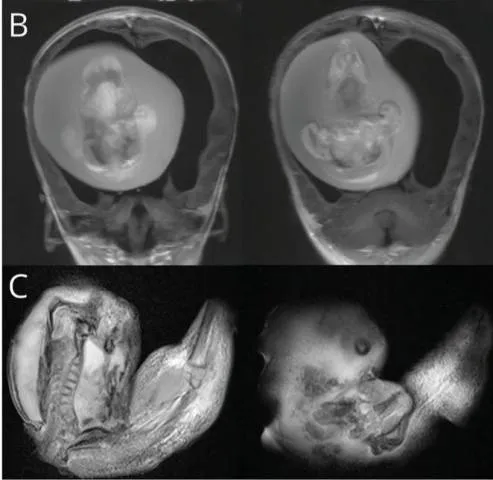

ମୁଣ୍ଡ ବଡ଼ ହୋଇଯିବା ସହିତ କେତେକ କାର୍ଯ୍ୟକଳାପ ପାଇଁ ପିଲାଟିର ମାଂସପେଶୀ କାର୍ଯ୍ୟ ନ କରିବାରୁ ତାକୁ ଡାକ୍ତରଙ୍କ ପାଖକୁ ଅଣାଯାଇଥିଲା। ତା’ର ମୁଣ୍ଡ ସ୍କାନ୍ କରାଯିବା ପରେ ଜଣାପଡ଼ିଲା ଯେ, ତା’ର ମସ୍ତିଷ୍କ ଭିତରେ ଜନ୍ମି ନ ଥିବା ଯାଆଁଳା ଭ୍ରୂଣ ରହିଛି। ଏହାଛଡ଼ା, ସେ ଭ୍ରୂଣ ଦୁଇଟିରେ ଶରୀରର ଉପର ଅଙ୍ଗପ୍ରତ୍ୟଙ୍କ ବିକଶିତ ହେବା ସହିତ ହାଡ଼ ଓ ଆଙ୍ଗୁଠି ଭଳି କଢ଼ି ସବୁ ଗଜୁରି ଥିଲା।

Image Courtesy of India Todayଉକ୍ତ ଭ୍ରୂଣ ଦୁଇଟିର ଗୁଣସୂତ୍ର କ୍ରମ ନିରୂପଣ କରିବା ପରେ ଜଣାପଡ଼ିଲା ଯେ, ସେ ଭ୍ରୂଣ ଅବସ୍ଥାରେ ଥିବା ପିଲା ଦୁଇଟି ମଧ୍ୟ ଏହି ପିଲାର ଯମଜ। ଡାକ୍ତରୀ ଭାଷାରେ ‘ଫେଟସ୍-ଇନ୍-ଫେଟୁ’ ଅବସ୍ଥାରେ ଏଭଳି ଘଟିଥାଏ। ସାଧାରଣରେ ଏହାକୁ ଗୋଟିଏ ପିଲାର ଭ୍ରୂଣରେ ଆଉ ଏକ ଭ୍ରୂଣ ପରି ଦିଶୁଥିବା ମାସଂ ଟିସ୍ୟୁ ଜମିବା କହନ୍ତି।

ସମଗ୍ର ବିଶ୍ବରେ ଏଭଳି ଘଟଣା ୧୦ ଲକ୍ଷ ଶିଶୁଙ୍କ ମଧ୍ୟରେ ଜଣକ ଠାରେ ଦେଖାଯାଇଥାଏ।